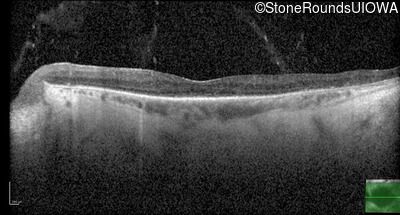

Optical Coherence Tomography - Right - 20/25 +1

Exemplar / OCT Stack